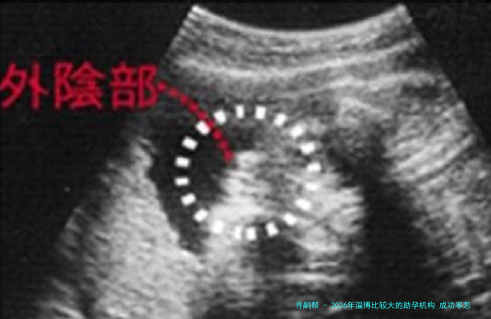

下列表格汇总了2026年淄博地域主要助孕机构的关键信息,供您参考。

应当留意的是,成功率受年纪、各别健康状态等多种要点影响,以上数据为鉴于公开信息的综合参照。建议您结合自我具体情况,与医疗专业人士进行透彻交流后作出选择。